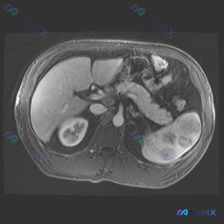

最近看到一张腹部MRI的T2加权轴位片,最初的焦点是“脾脏病变”,但仔细梳理下来,觉得这个病例的阅片思路特别有借鉴意义,整理出来和大家分享。 先看病例的影像客观发现 - 肝脏:右叶可见一处类圆形高信号影,边界清晰锐利,信号均匀; - 脾脏:外后缘可见一处类圆形高信号影,边界清晰,信号均匀; - 左肾...

看到一份很有意思的影像读片案例,用户的问题聚焦在“脾脏病变”,但影像本身却给了我们一个完全不同的方向,整理一下思路和大家分享。 --- 先看影像基本情况 - 序列:腹部MRI T2加权轴位像 - 用户焦点:脾脏病变 关键影像发现(按实际读片顺序) 1. 肝脏、胆囊、胰腺:未见明显异常信号或肿块,胆管...

今天整理了一个挺有意思的影像读片病例,有点「答非所问」但非常考验临床思维,和大家分享一下思路。 --- 病例背景与影像资料 用户明确问的是「脾脏病变」,提供的是一张腹部MRI-T2加权轴位图像。 先直接说针对「脾脏」的第一判断: 👉 在这张图像上,脾脏实质信号均匀,皮髓质分界清晰,没有看到局灶性的高...